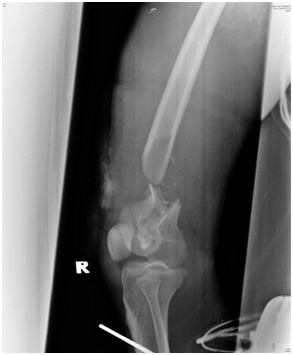

The purpose of this case report is to demonstrate that despite the severity of the injury, good union and functional outcome is achievable using the relatively simple technique of distal femur plating with locking plate augmented with autogenous non-vascularized fibula bone graft.We presented a case of a 20-year-old man who had an alleged motor vehicle accident. He presented to the emergency department with pain and bleeding of the right thigh. On examination, Glasgow Coma Scale score was 15 of 15. There was a deep laceration wound at the anterolateral aspect of his distal right thigh measuring 8cm by 4cm. There was deformity, local tenderness, and abnormal mobility in the distal part of the thigh but no distal neurovascular deficit. Radiographs of the right femur revealed a severely comminuted supracondylar fracture with bone loss and intraarticular involvement (Figure 1A & 1B). The fracture was classified as AO type 33-C3.